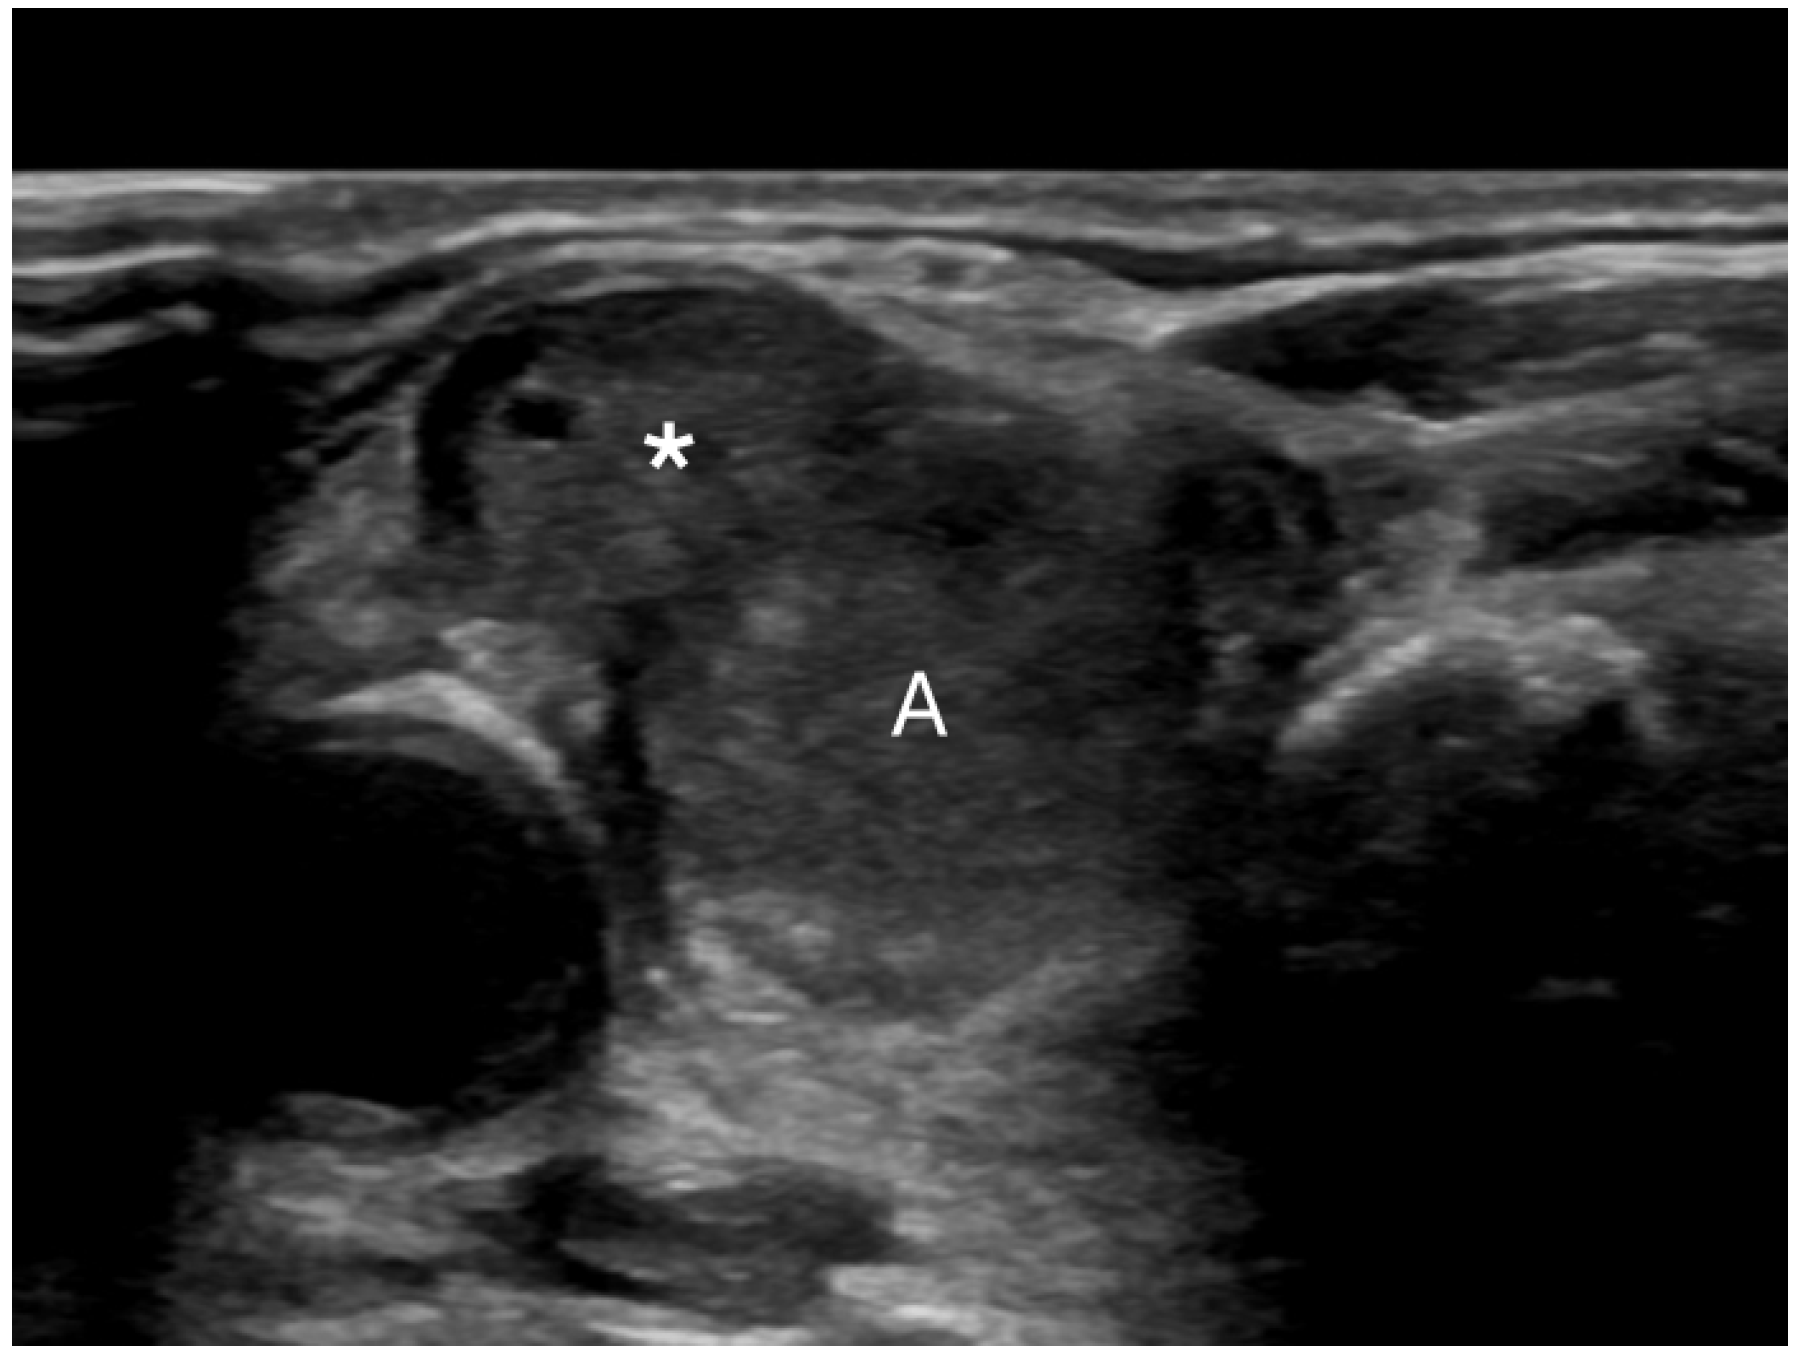

PEF refers to distinct echogenic dots ≤1 mm within a thyroid nodule (Figure 2) [24]. Unlike macrocalcifications, PEF do not cast a posterior acoustic shadow, although they can be associated with small comet tail artifacts. It is important to differentiate PEF from echogenic foci > 1 mm, which can be associated with more pronounced V-shaped comet tail artifacts; the latter are characteristic findings in benign colloid nodules [24]. The underlying etiology in PEF is unclear; in some instances, these may represent psammoma bodies in papillary cancers, while in others, they may indicate the back wall of microcysts [24]. PEF were observed in 64.7% of the malignant nodules compared to only 9% of the benign nodules in our study. Multivariate regression revealed that PEF were associated with a significant cancer risk, yielding an OR of 11 (95% CI, 6.4 to 18.8), at p < 0.001. Our findings agree with the literature. Nabahati et al. conducted a study involving 1129 nodules and found a significant correlation between PEF and malignancy, with ORs of 3.7 (95% CI, 2.3 to 5.8) in a univariate analysis and 1.9 (95% CI, 1.1 to 3.2) in a multivariate analysis [48]. Sohn et al. examined 1018 nodules and found a significant correlation between intra-solid PEF without comet tail artifacts and cancer risk, yielding an OR = 8.1 (95% CI, 3.6 to 17.9), at p < 0.001 [49]. Lastly, Ha et al. studied 1112 nodules and reported that PEF with comet tail artifacts were associated with a malignancy rate of 77.8% in solid and predominantly solid nodules [50].

Figure 2. A malignant nodule (arrow) with punctate echogenic foci.